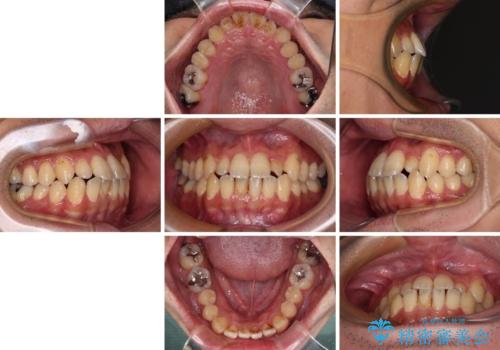

内側に引っ込んだ歯を治したい インビザラインの矯正治療

- 前歯のデコボコとクロスバイトを治したいとのことで来院された患者様です。

上下顎ともに歯列全体の側方拡大とIPR(歯と歯の間を削る)によってデコボコとクロスバイトが解消するように設計し、インビザラインにより治療を行うこととしました。

反対咬合特有の治療途中の前歯の干渉が長く続き、治療中に食事をとりにくく、ご迷惑をおかけしました。

前歯の咬み合わせの調整などを行い、安定した咬み合わせに仕上げることができました。